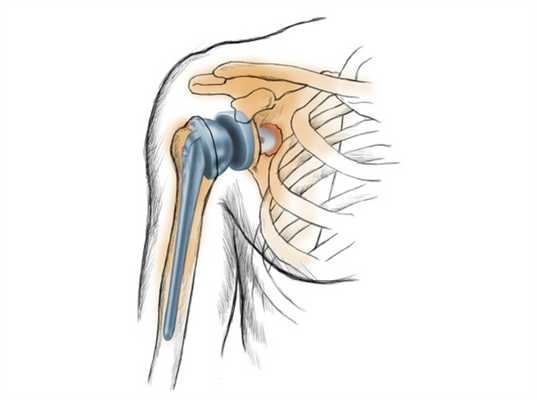

Полная замена илитотальное эндопротезирование плечевого сустава. Стержень плечевого протеза может закрепляться на цементе или бесцементно. © Gelenk-Klinik

Полная замена или тотальное эндопртезирование плечевого сустава. Стержень плечевого протеза может закрепляться на цементе или бесцементно.

Полная замена плечевого сустава

При полной замене плечевого сустава заменяются оба компонента сустава: плечевая головка и суставная впадина. Это самый распространенный метод замены плечевого сустава. При износе обеих поверхностей сустава, как плечевой головки так и суставной впадины, необходим полный эндопротез. При таком методе замены удаляется сегмент плечевой головки, наиболее близкий к суставу. Затем внутренняя часть (пространство костного мозга) плечевой кости подготавливается для внедрения ножки протеза.

Ножка протеза имплантируется вовнутрь кости. Одним из наиболее тяжелых осложнений при полной замене плечевого сустава является ослабление гленоидного компонента. Это ведет к возникновению боли и ограничению подвижности.

В зону, где была суставная головка, устанавливают протез с наличием шаровидного элемента, который расположен на ножке. Ее помещают внутрь костного канала. В месте, где была впадина, укрепляют пластмассовую часть конструкции, имитирующую поверхность хряща. Ножку протеза имплантируют внутрь кости.